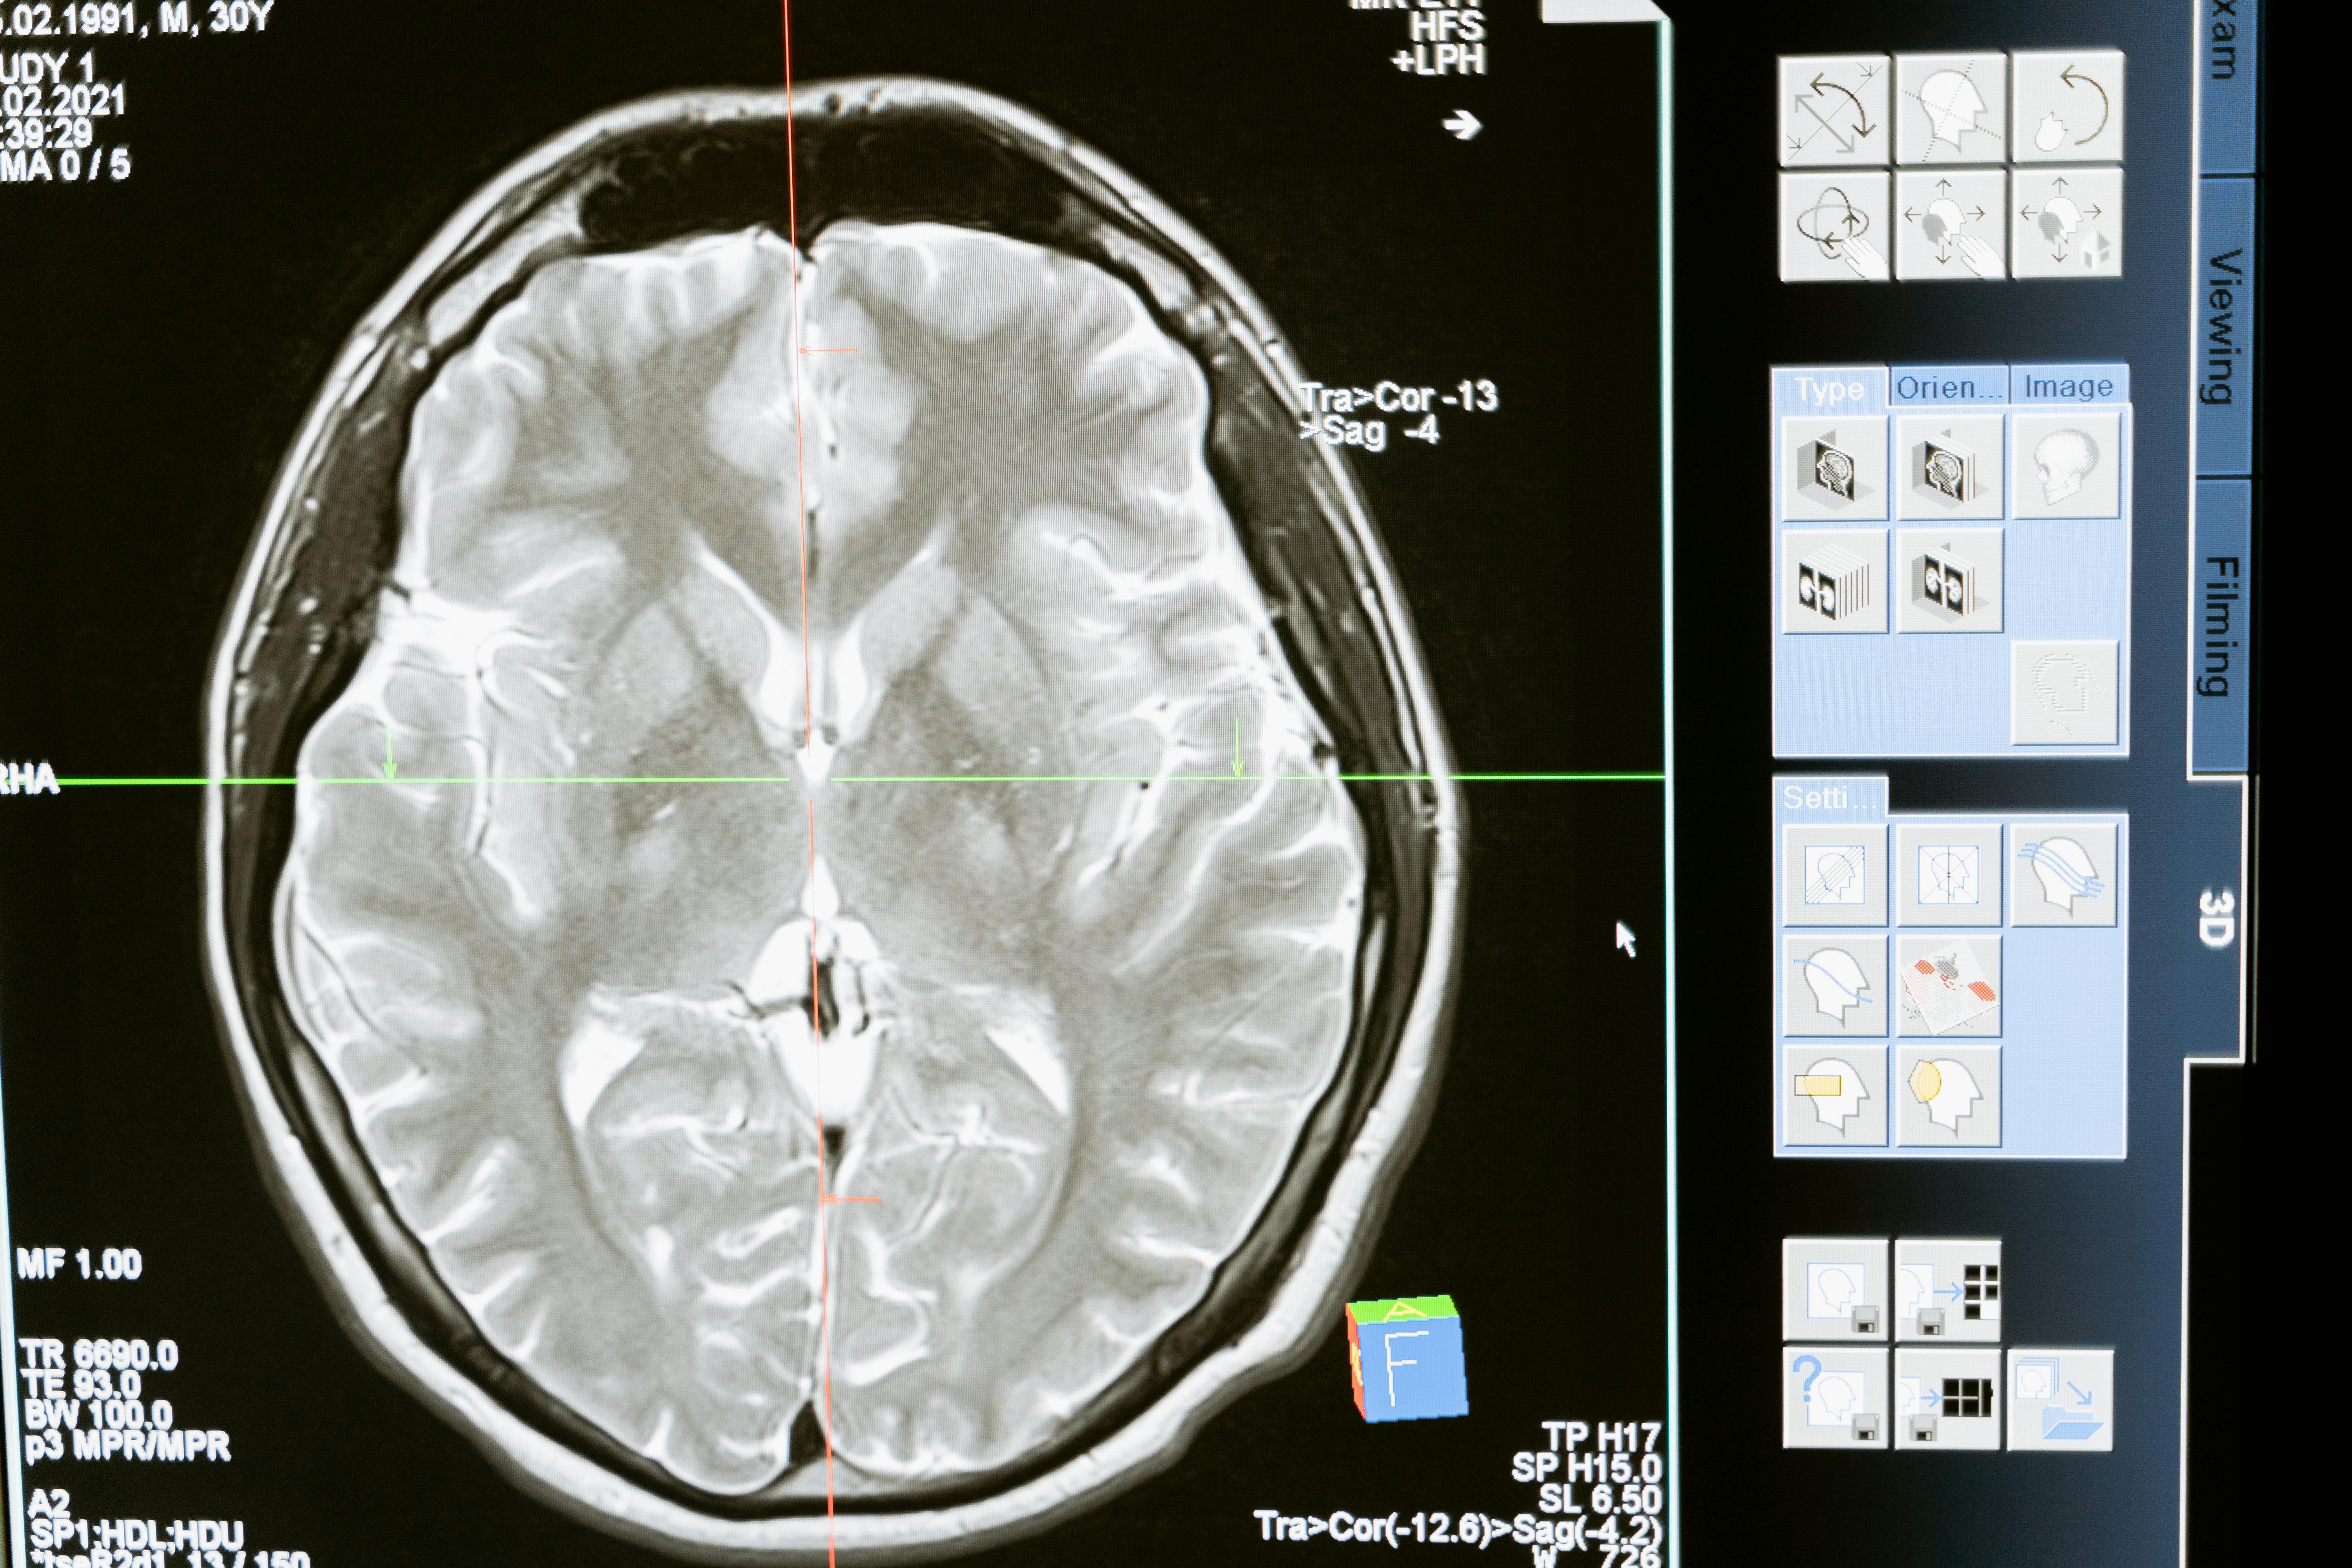

Neuroradiology